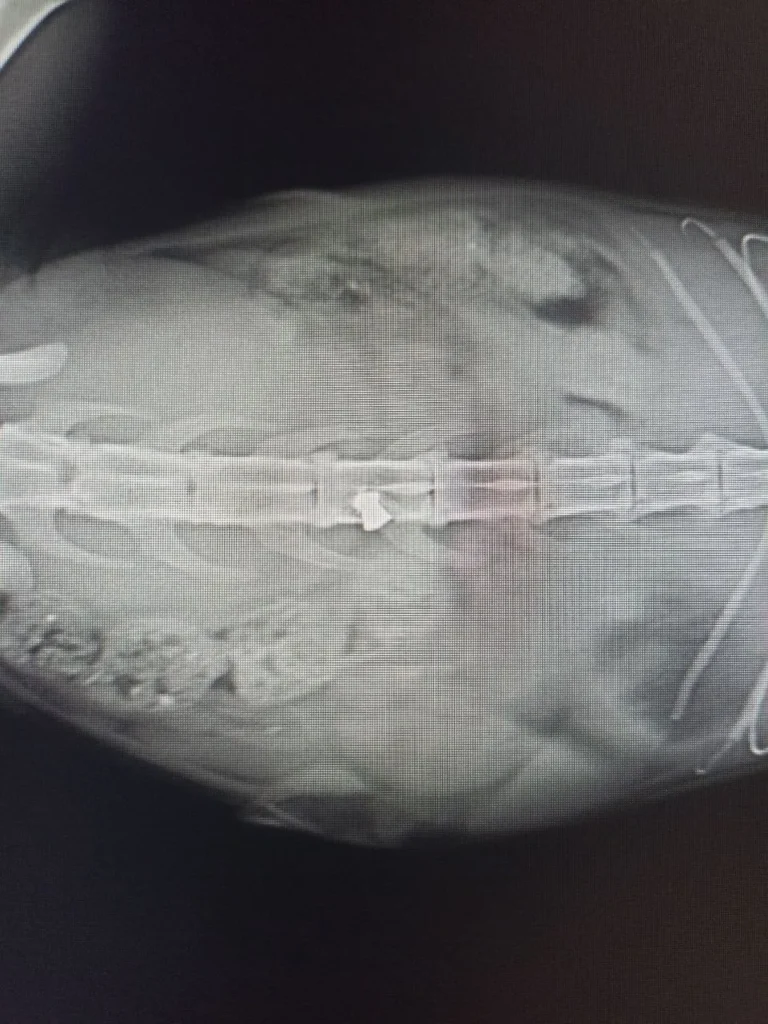

У безпритульного кота вистрелили з пневматичної зброї, куля потрапила у спинний мозок. Тваринка доповзла до підвалу, де її потім і знайшли.

Нині кота, якого назвали Кімом, прооперували, дістали кулю. Він не відчуває половини тіла та перебуває в тяжкому стані.